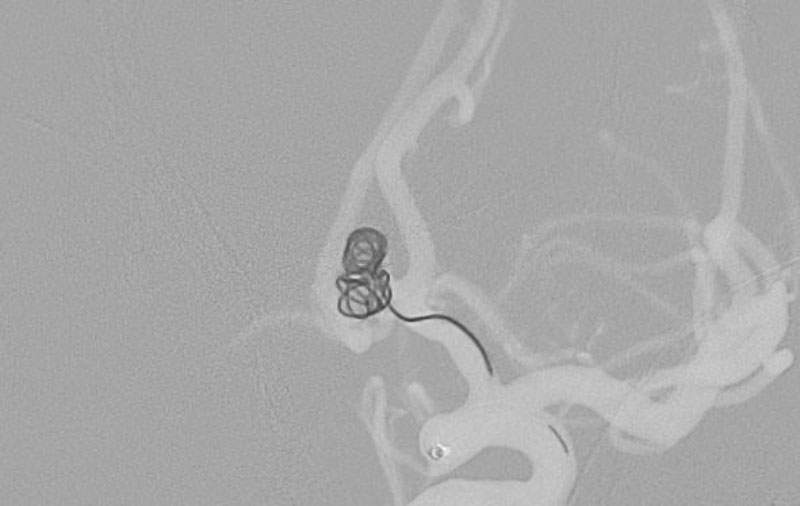

'25年10月

くも膜下出血

右前交通動脈瘤破裂

60代

救急外来

No.1587 手術前

No.1587 手術中

No.1587 手術後